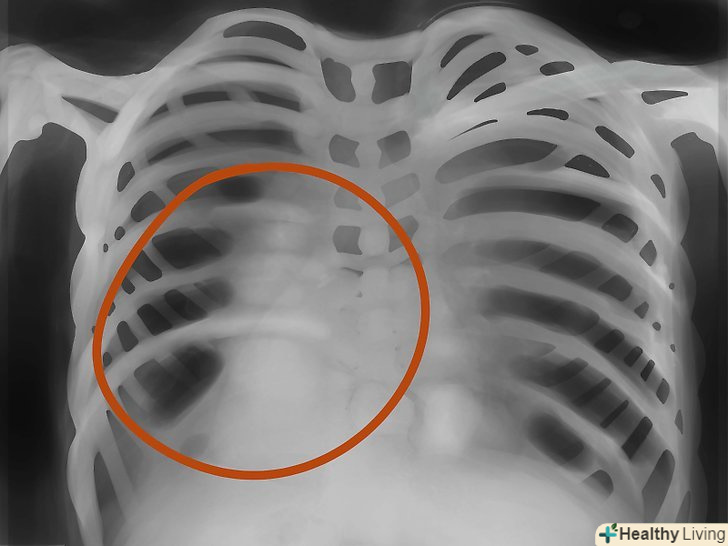

Контур серця.зверніть увагу на біле місце між легенями-серце. У нормі на серце повинно припадати менше половини ширини грудей.- Якщо серце на pa-знімках нагадує пляшку води-потрібна комп'ютерна томографія, щоб виключити наявність ексудату в області перикарда.